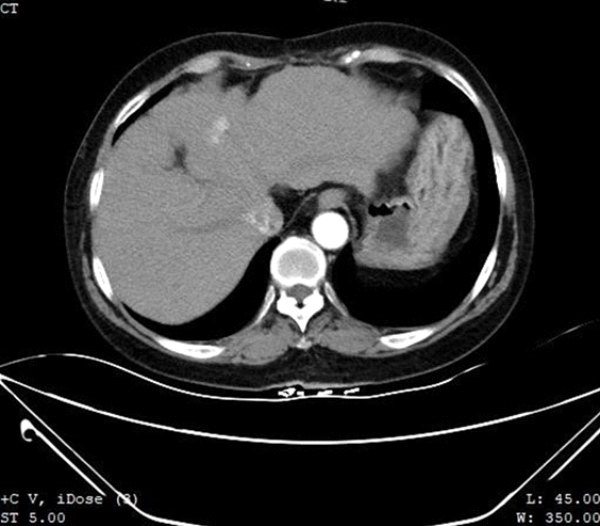

A 64-year-old female with a 30+ year history of hepatitis B and 6 years post S7 partial hepatectomy and splenectomy for primary hepatocellular carcinoma presented to our department after an MR examination performed in our hospital 3 months ago indicated liver cirrhosis and suspected malignant nodules in S4 of the liver. Re-examination using contrast-enhanced CT showed a mildly hypodense foci about 1.5 cm in diameter in S4 of the left liver lobe (Fig. 1) with obvious uneven enhancement in the arterial and portal phases and mild washout in the venous phase, suspicious for recurrent hepatocellular carcinoma.